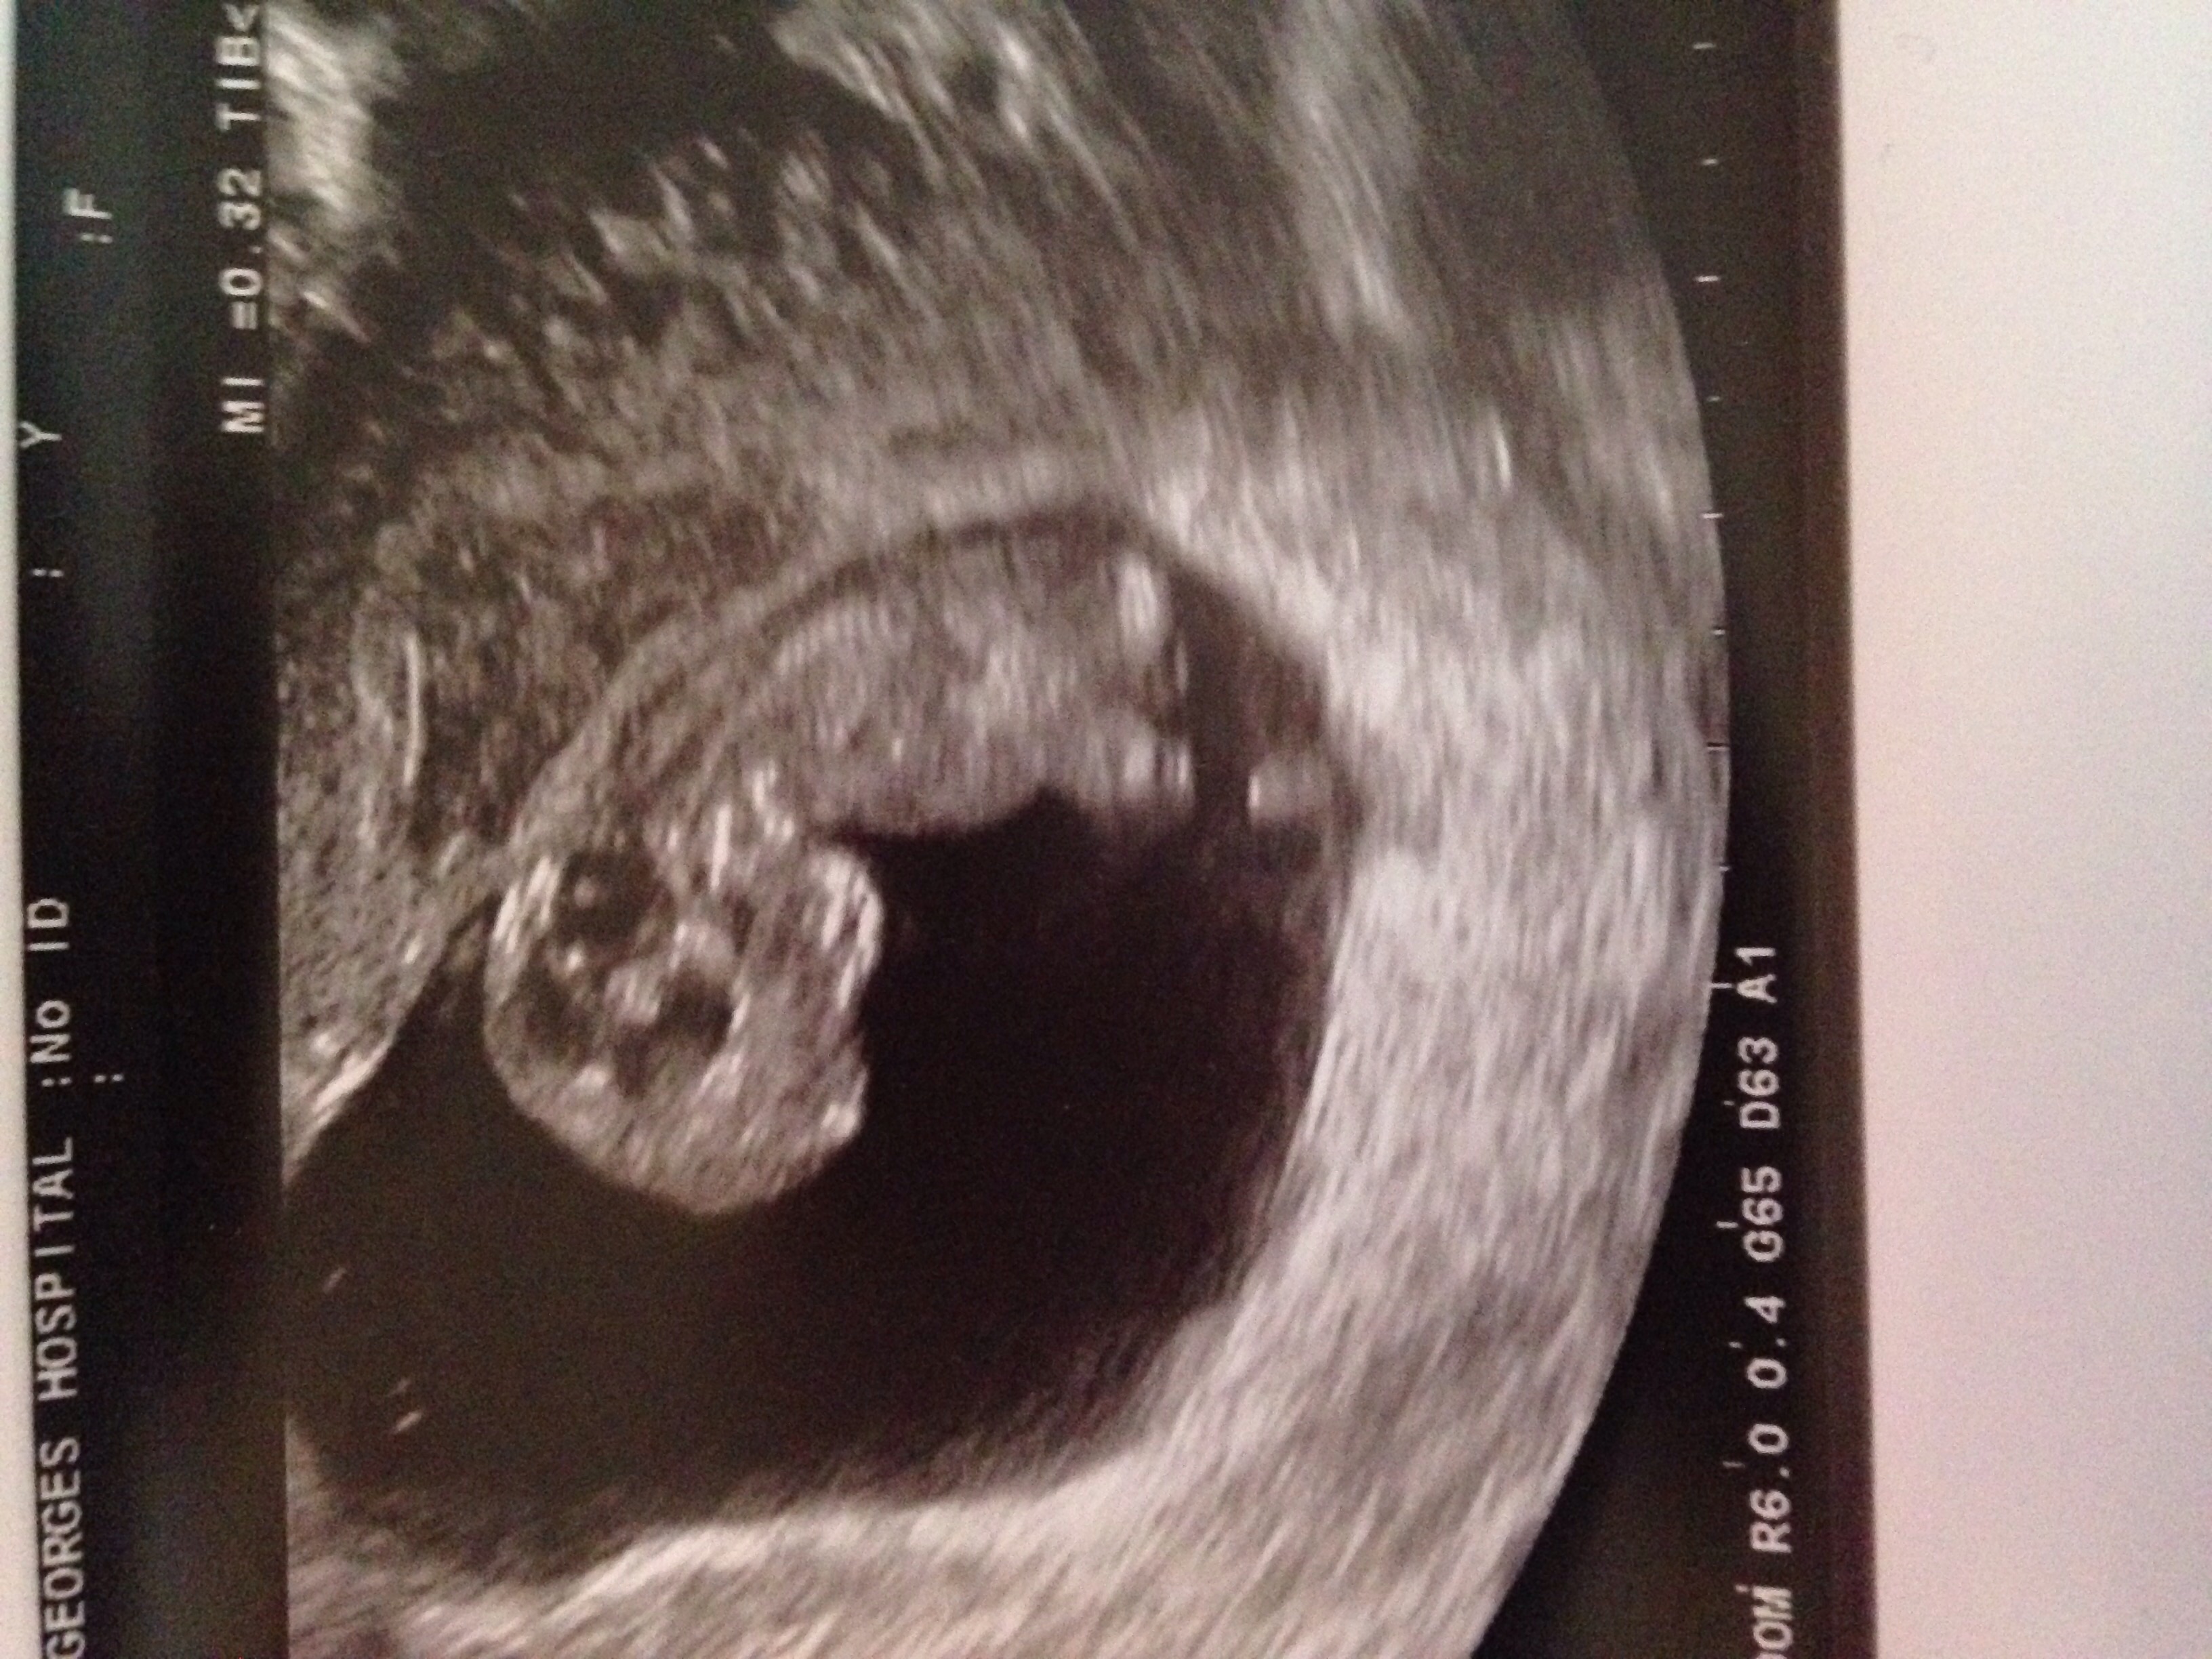

Yesterday evening I was making some food in the kitchen when I felt myself with a flow of bleeding (felt like a heavy period) I rushed to the toilet and sure enough I was bleeding a lot, I put a pad in and laid on my back to try and slow it down. My boyfriend rushed home from work and took me to A&E, they told me to come back early the next morning to the early pregnancy unit for a scan. I went for my scan and everything was great, we saw the baby's heartbeat and even got a picture of our little baby, she said the sizing is all spot on and everything looks good. Obviously I feel so much relief but I still have this niggling feeling in the back of my mind that there's still time for something to go wrong!